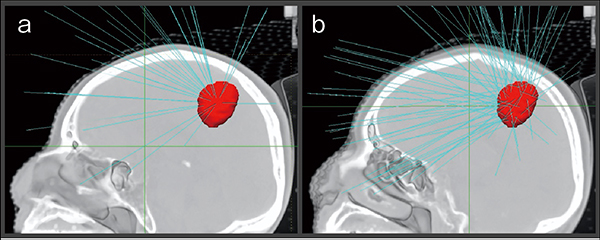

このように利点の多い機器ではあるが,一方で,一般的なリニアックと比較すると最大照射野が小さく,通常のコリメータ(fixed/Iris collimator)では最大6cmの円形照射野になり,MLCを使用しても矩形照射野11.5cm×10cm程度しかないため,広範囲な照射は苦手としている(図3 a)。通常は三次元的に多方向から照射し,かつ一点にビームを収束させないnon-isocentricな照射(図3 b)を行うため,最大照射野を超える大きさでも照射は可能だが,その分どうしても1回あたりの照射時間が長くなってしまうことになる。結局は,限られた狭い範囲での照射に関して優位な機器ということになる。

図3 サイバーナイフにおける照射方法の違い

a: isocenterを持つ照射

b: isocenterを持たない照射(non-isocenter)

aは短時間で照射可能だが大きな病変には不向き。bは形が複雑で大きな病変にも対応できる。通常はbを用いる。